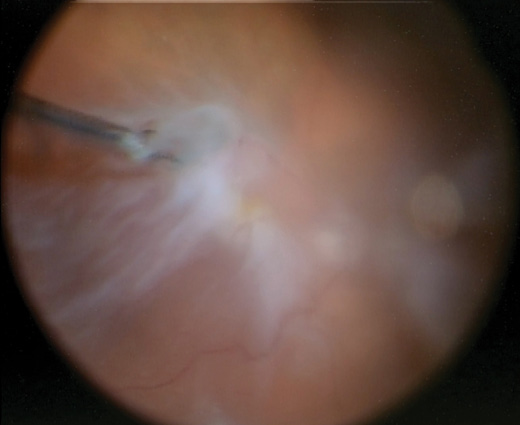

A small amount of diluted triamcinolone acetonide (Kenalog, Bristol-Myers Squibb) 1:3 was injected to stain the membranes associated with the starfold, as well as the ERM in the macula. Disposable internal limiting membrane (ILM) forceps were used to lift the edges of the membranes before switching to 25-gauge Grieshaber MaxGrip forceps (Alcon). The starfold temporally was difficult to fully peel given the presence of the stretch hole (Figure 2). Ultimately, I decided to create a draining retinotomy with the vitrector in that area, given its peripheral location, and to excise the starfold at the same time.

Figure 2. Intraoperative image of the starfold adjacent to the stretch hole in the temporal periphery.